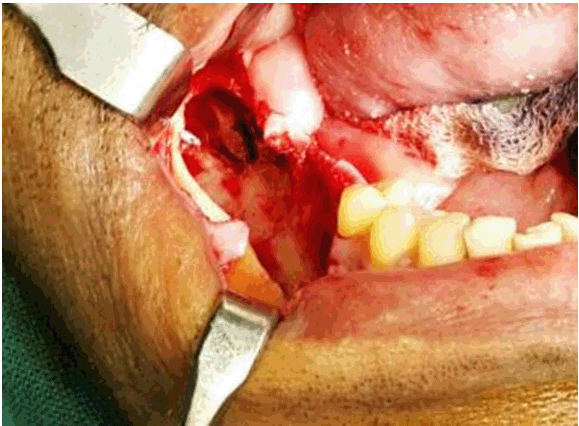

Surgical enucleation and curettage of the lesion was planned under general anesthesia. Crevicular incision was placed from 45 to 47 and extended onto the ascending ramus of the mandible. Full thickness mucoperiosteal flap was reflected, extraction of 46 and 47 was performed. There was thinning of buccal cortical bone. De-roofing of the cyst was done to expose the cystic cavity. Careful enucleation and curettage of the lesion was performed (Figure 2). Impacted 48 were removed and the entire bony cavity was thoroughly irrigated with hydrogen peroxide and saline. Enucleated tissue specimen was sent for histopathological examination. Postoperatively wound healing was satisfactory and orthopantomogram at sixth month follow-up visit revealed new bone formation with no recurrence (Figure 4), still the case is under follow-up.

Figure 2: Bony cavity after enucleation.